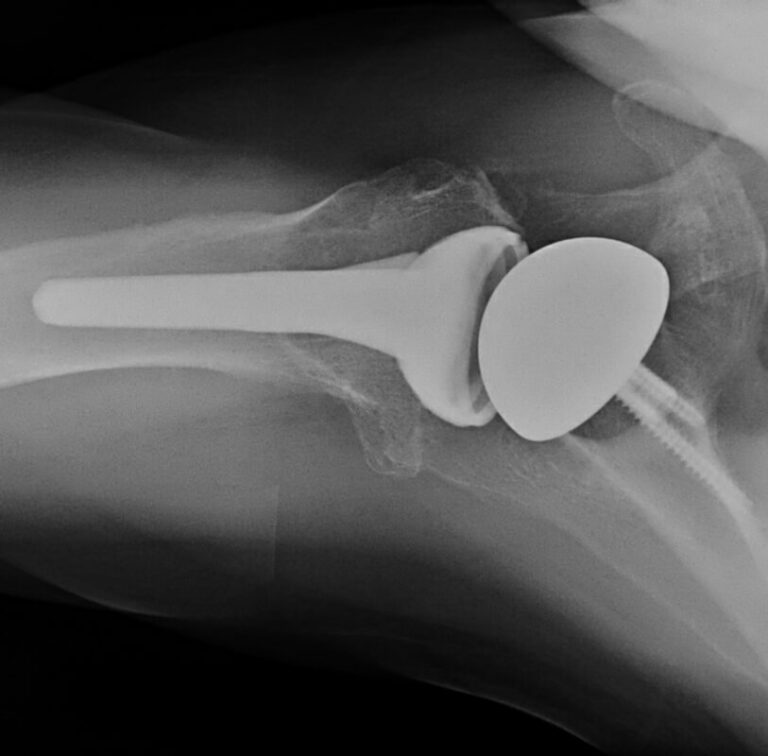

DePuy, DeltaXtend